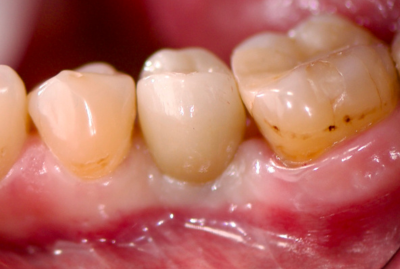

КЛинический случай максима хышова

Удаление зуба 26. Установка имплантатов VEGA+ в позиции 25 и 27.

✔️ В позицию зуба 27 установлен VEGA+ RV 4.6x10 mm. Получена первичная стабильность 20 Н/см. Установлен винт-заглушка

✔️В позицию зуба 25 установлен VEGA+ RV 4.1x14 mm. Получена первичная стабильность 50 Н/см. Установлен винт-заглушка.